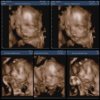

31 uker ♥

Tenk det..9 uker igjen!! Kun 66 små dager til termin.. helt ufattelig ♡ Gleder meg så vanvittig til å kosemose med Jonasen vår. Er sååå klar for å starte på babyperiode igjen! Blir også helt fantastisk å se Sindre som pappa og Celine som storesøster ♥ Gleder meg virkelig til slutten av februar altså!

Lillebror er på vei ♡ 21. Februar 2014